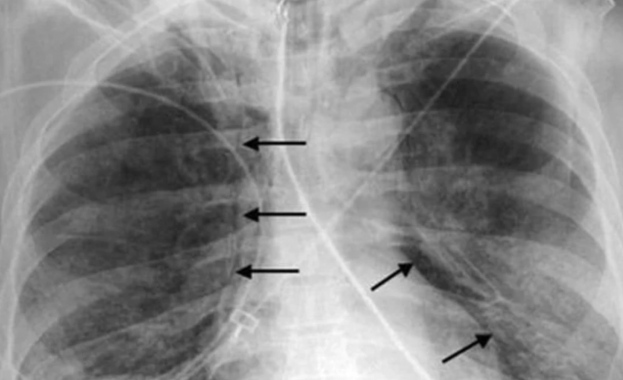

Засегнат е 67‑годишен мъж, който е приет в болница на 6 април с двойна бронхопневмония. След проведено лечение пациентът е изписан седмица по‑късно.

Ку‑треската е бактериална инфекция, причинена от Coxiella burnetii. Заразяването най-често става чрез вдишване на прахови частици, съдържащи бактерията, контакт с мляко, урина, изпражнения или секрети на заразени животни (обикновено овце, кози, говеда).